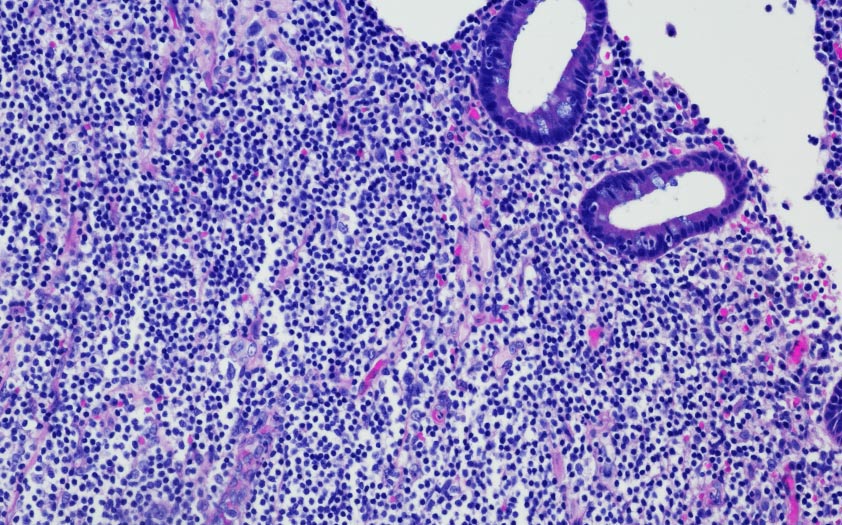

El linfoma difuso de células B grandes (LDCBG) es el subtipo de linfoma no Hodgkin agresivo más común (representa casi el 50% de todos los linfoma no Hodgkin agresivos y el 30% de todos los linfoma no Hodgkin), con una edad mediana de aparición de 65 años.

Linfoma de Burkitt

Progresión muy rápida, y en el que pueden distinguirse formas esporádicas que suponen en torno al 30% de todos los linfomas infantiles o bien formas asociadas a la infección por el virus del VIH).